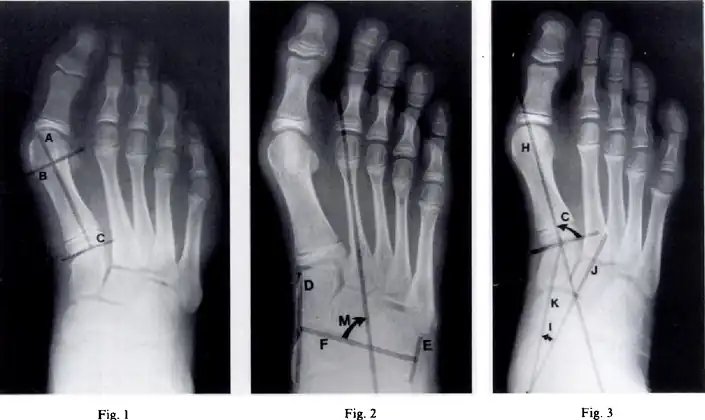

- Metatarsus (primus) varus-Fig 1 - Length of the lateral cortex of the first metatarsal, Fig 2-metatarsus adductus angle measures the position of the lesser tarsus relative to the midfoot, Fig 3- the cuneiform angle

- A Sgarlato's angle of more than 15° indicates pigeon toe.[9]

Pigeon toe can be diagnosed by physical examination alone.[10] This can classify the deformity into "flexible", when the foot can be straightened by hand, or otherwise "nonflexible".[10] Still, X-rays are often done in the case of nonflexible pigeon toe.[10] On X-ray, the severity of the condition can be measured with a "metatarsus adductus angle", which is the angle between the directions of the metatarsal bones, as compared to the lesser tarsus (the cuneiforms, the cuboid and the navicular bone).[11] Many variants of this measurement exist, but Sgarlato's angle has been found to at least have favorable correlation with other measurements.[12] Sgarlato's angle is defined as the angle between:[9][13]

- A line through the longitudinal axis of the second metatarsal bone.

- The longitudinal axis of the lesser tarsal bones. For this purpose, one line is drawn between the lateral limits of the fourth tarsometatarsal joint and the calcaneocuboid joint, and another line is drawn between the medial limits of the talonavicular joint and the 1st tarsometatarsal joint. The transverse axis is defined as going through the middle of those lines, and hence the longitudinal axis is perpendicular to this axis.

This angle is normally up to 15°, and an increased angle indicates pigeon toe.[9] Yet, it becomes more difficult to infer the locations of the joints in younger children due to incomplete ossification of the bones, especially when younger than 3–4 years.